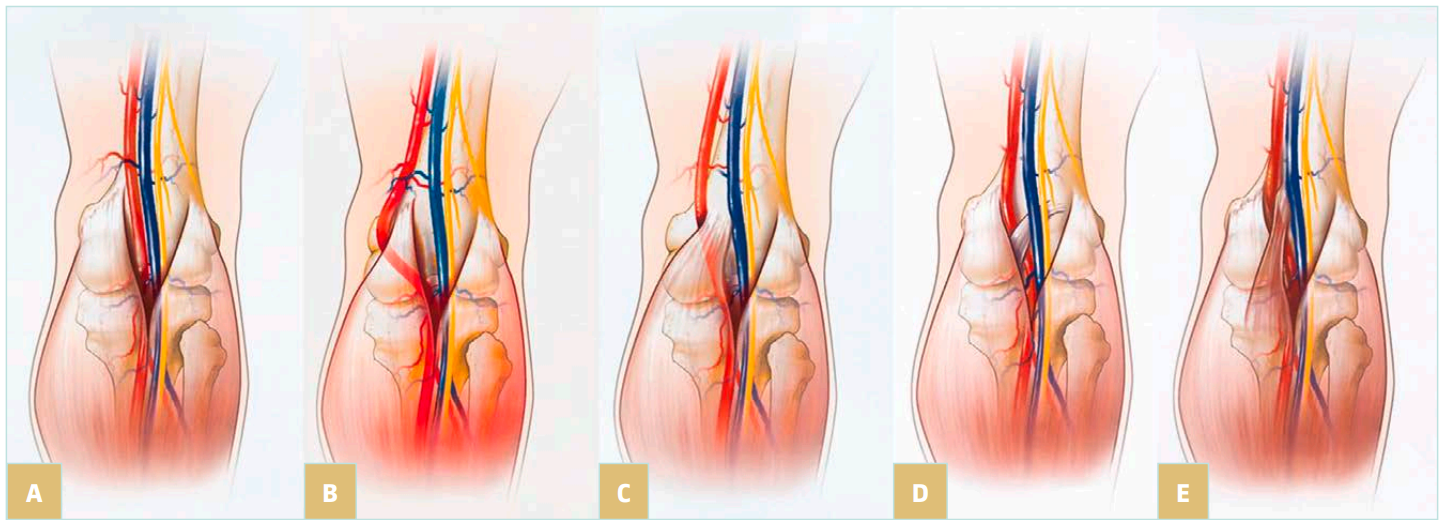

In the tiptoe test, the patient is standing, preferably on a phlebologic stool, with only the anterior part of his feet on the edge. The US probe is placed longitudinally on the popliteal fossa to identify the popliteal vein. The patient is asked to slowly move up and down: compression of the vein by muscular structures of the sural triceps is confirmed by flow restriction in color or power Doppler mode. We consider that clinically significant compression implies a positive test in both extension and flexion of the foot (Figure 3).

Figure 3. Ultrasound image from the tiptoe test. (Upper image) foot extended. (Lower image) foot in neutral position.